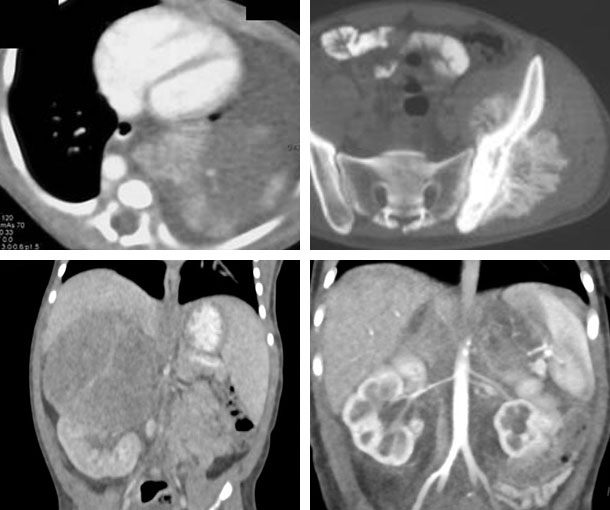

Neuroblastoma CT Findings

- Most commonly found in the retroperitoneum but can be seen in many parts of the body

- Commonly arise in the adrenal gland

- Large and heterogeneous

- Lobulated mass

- Most cases have calcification

- Little enhancement

- May have areas of low attenuation

- Encasement and/or compression of abdominal vessels